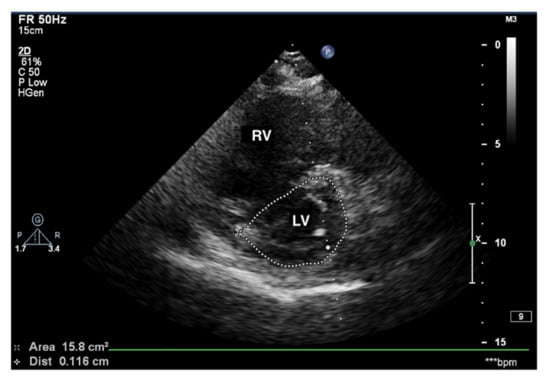

Transthoracic echocardiography (TTE) in a patient with advanced PAH is conspicuous by the RV cavity′s abnormal shape, especially in the parasternal short axis (Figure 5). The RV assumes a spherical shape, and the interventricular septum protrudes into the LV, forming the so-called D-shape sign [18]. If a D-shaped LV appears in the end-diastolic phase, it suggests RV pressure overload, whereas a D-sign shape in diastole suggests RV volume overload [19,20].

Figure 5.

D-sign, enlarged right ventricle, ventricular septum displaced towards LV. 2D-TTE, short-axis view (SAX). LV: left ventricle; 2D-TTE: two-dimensional transthoracic echocardiography.